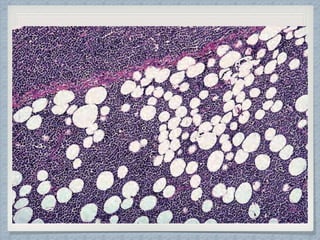

Gross Findings

Of Nephroblastoma

Blastematous elements

Epithelial elements

Mesenchymal /Stromal

elements

Neural elements